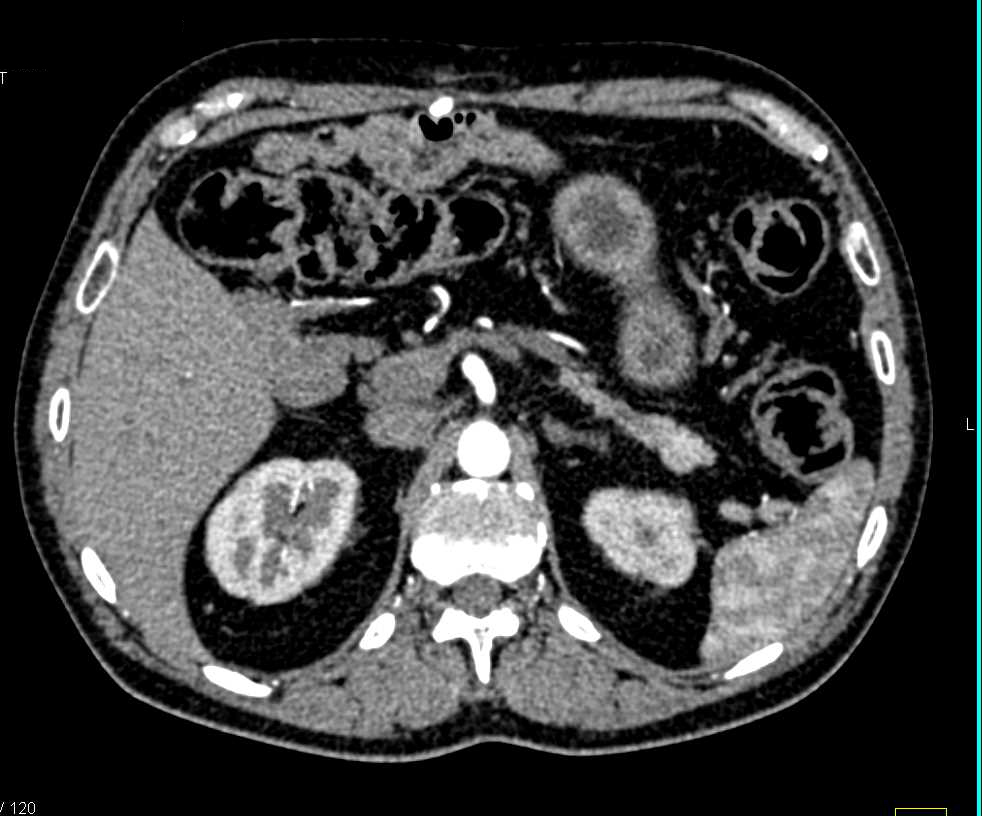

MCN (Mucinous Cystic Neoplasm) Body of the Pancreas